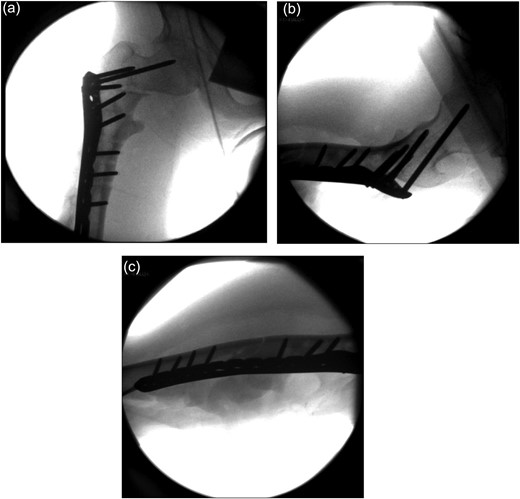

Under general anaesthesia, open reduction and internal fixation using a 10 hole philos plate was performed with the patient in a supine position on the traction table utilizing a lateral approach. Using C-arm image intensification, the height of the plate was judged, then applied to the bone and secured both proximally and distally to the fracture with proximal locking screws inserted where possible (Fig. 2a–c). Securing the cephalic segment of the philos plate to the proximal femur proved challenging due to the femoral neck defect left by the removal of the blade plate. Final reduction was judged to be near anatomical with the wound thoroughly irrigated with saline before closure. Post-operative treatment included IV antibiotics with mobility instructions unnecessary due to the patient's non-ambulatory status. The patient was discharged after 5 days with a follow-up period over 11 months. There were no post-operative complications during this time and radiographs showed an anatomically healed fracture (Fig. 3).

Image intensifier intra-operative AP highlighting 10 hole PHILOS applied with near anatomical reduction (a–c).